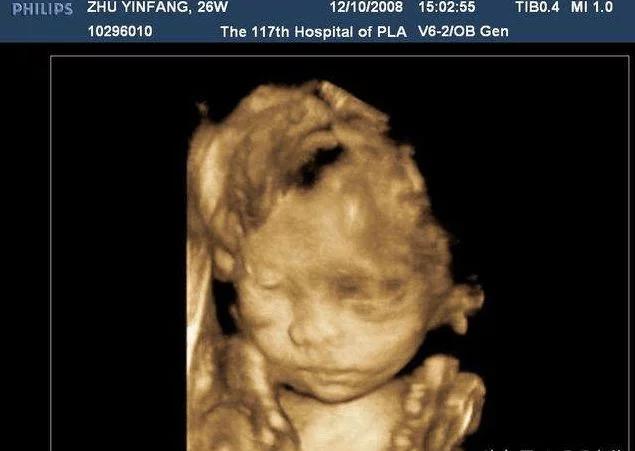

42天时去做第一次b超,就发现了有一点不对的地方,就是孕囊在左宫角那里,也许很多人,还不太了解,就是还没有到最里面,宝宝就在那里扎根了,如果乐观长长就进去了,如果不乐观,医生说就证明自己怀孕过。当然医生也不能说的那么绝对,就说明天再来一次,有专家来,再给看看。谁知这一来二去做了4次b超,让本来担心的小小,越来越担心了,心情也不再好了,这几天就哭了好几回,医生说先回家视察,只要不出血,就没有什么问题,再大一点再来视察,最主要的就是心情了。